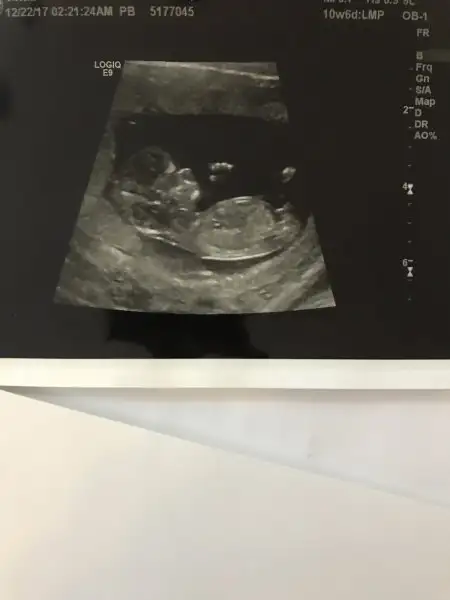

Kızlar merhaba.Ultrason resimlerinden cinsiyet tahmini yapabilen var mı aranızda? Bir sürü teoriler var iyice kafam karıştı. Aslında öğrenmenin önemi yok da insan merak ediyor işte ☺️

12 haftada dogru ve guzel resimle nuba bakilir ona göre tahmin yapilir